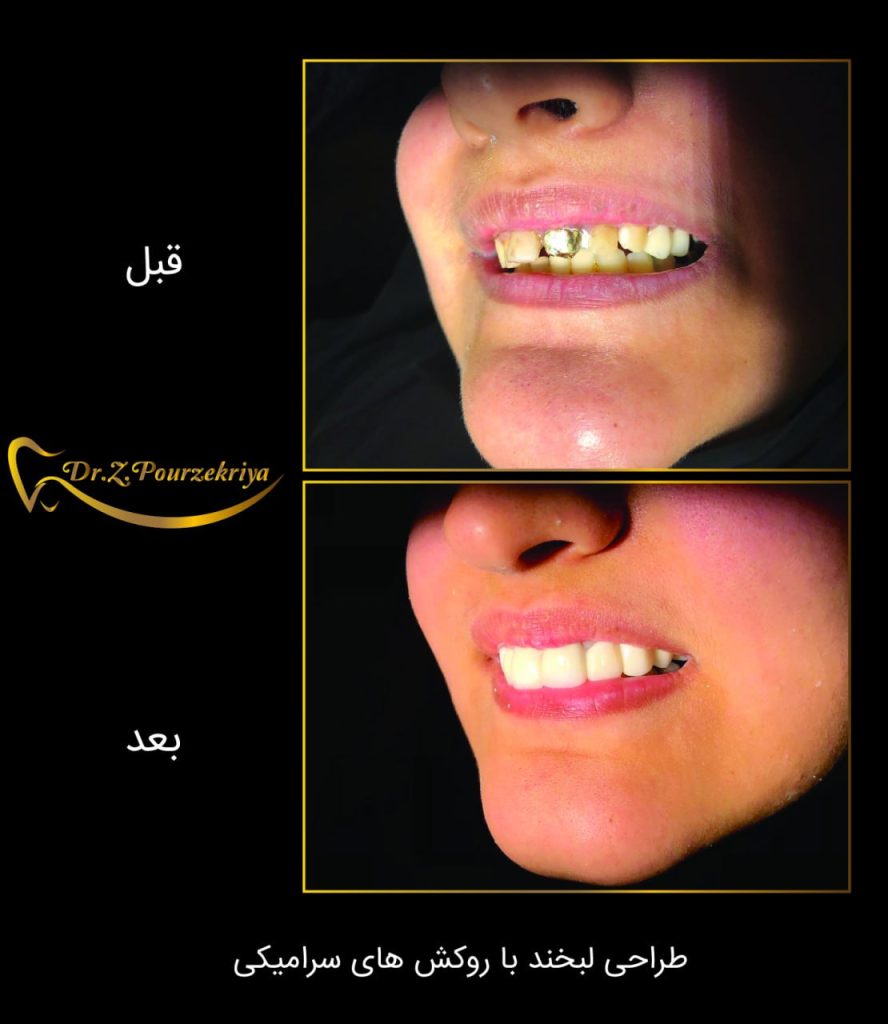

روکش های سرامیکی دندان

با ماندگاری طولانی

دندان های درخشان لبخندی منحصر به فرد

روکش های سرامیکی دندان

با ماندگاری طولانی

نمونه های درمان

دکتر زکیه پور ذکریا، جراح دندانپزشک و ایمپلنتولوژیست :

ورضایت مراجعین برایم بزرگترین تبلیغ محسوب میشود